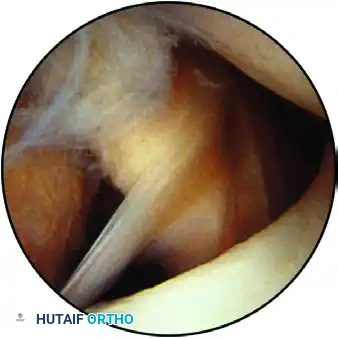

View of the anterior structures: The superior glenohumeral ligament and subscapularis tendon are visible on the right, with the middle glenohumeral ligament located inferiorly.

The arthroscope is then directed over the anterior labrum toward the anterior "soft spot"—a triangular interval bounded by the biceps tendon proximally, the subscapularis tendon distally, and the glenoid articular surface inferiorly.

The Buford complex: A normal anatomical variant showing the insertion of a cordlike middle glenohumeral ligament directly into the biceps anchor, with an absent anterosuperior labrum.

Snyder described the Buford complex, a variant where the middle glenohumeral ligament (MGHL) is thickened and cordlike, inserting directly into the biceps tendon, leaving a bare area on the anterosuperior glenoid devoid of labral tissue. Recognizing this prevents the catastrophic error of surgically "repairing" a normal Buford complex, which would severely restrict external rotation.